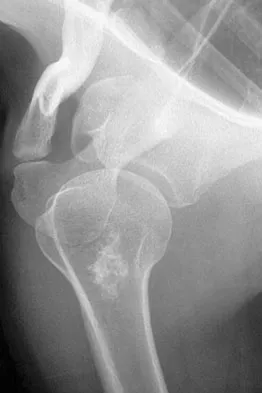

Figure 6 shows the radiograph of a 14-year-old baseball player who felt a pop and had an immediate onset of pain in his elbow after a hard throw from the outfield. The best course of action should be to

The valgus stress at the elbow caused by throwing strains the medial collateral ligament. The medial epicondyle, on which the ligament inserts, is the last ossification center to fuse to the distal humerus, and acute avulsion of the medial epicondyle can occur in adolescents. If the elbow is allowed to heal in a displaced position, valgus instability and loss of elbow extension may result. Valgus instability is especially problematic for the throwing athlete. Surgical treatment with rigid internal fixation is the treatment of choice for displaced medial epicondyle avulsion fractures. Valgus instability is prevented, and the rigid fixation allows for early range of motion. Case SL, Hennrikus WL: Surgical treatment of displaced medial epicondyle fractures in adolescent athletes. Am J Sports Med 1997;25:682-686.